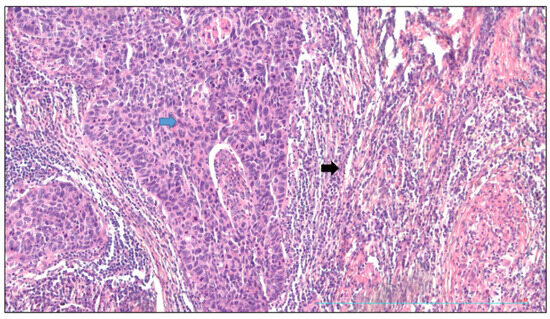

Figure 2 shows the squamous cell carcinoma of the lung with tumor proliferation surrounded by a peritumoral reactive stroma; the sign − signified the absence; the sign + signified the presence.

Figure 2.

Squamous cell carcinoma of lung and peritumoral stroma. Magnification ×20, HES staining. The tumor proliferation (blue arrow) was composed of dense masses of cohesive squamous cells of tumor origin. It was surrounded by a peritumoral reactive stroma (black arrow) consisting of a fibrous background and a dense lympho-plasmacytic infiltrate.